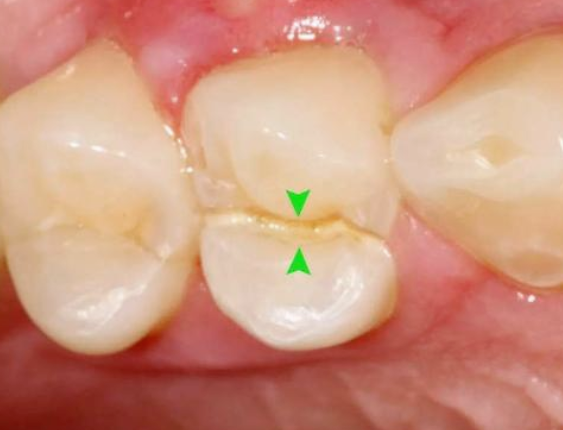

根管不做冠,早晚是后患!患者“不做冠”后牙齿劈成了两半!